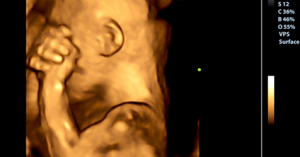

엄마가 슬퍼서 울 때 태아가 느끼는 감정이 있을까? 태아가 엄마의 배 속에서 느끼는 감정과 경험은 엄마와 직접적으로 연결되어 있다. 임신 기간 동안은 엄마는 아기의 전부다. 엄마 배 속에 있는 아기에게 가장 가까운 존재는 당연히 엄마다.

과학적으로, 임신 중에 아기는 엄마의 감정과 똑같은 감정을 똑같은 강도로 느낀다고 한다. 엄마가 슬퍼서 울면 아기도 똑같이 슬퍼한다. 마치 자기 자신의 슬픔과 고통인 것처럼 느낀다.

임신 기간 동안 아기는 태어나기 위한 준비를 한다. 캘리포니아주립대 얼바인 캠퍼스의 최근 연구에 참가한 과학자 중 한 명인 커트A. 샌드맨은, 아기는 엄마가 보내는 메시지를 느낀다고 한다. 이 연구는 엄마의 감정 상태가 아기의 태어나기 전과 후의 발달에 영향을 준다는 사실을 발견했다.

또한 엄마의 자궁 안에 있는 태아는 이 기간에 삶에 필요한 정보를 수집하면서 스스로 활발하게 성장하고 있다는 것을 발견했다. 이는 매우 특별하다.

그리고 엘리시아P. 데이비스와 로라 M. 글린이 참여한 이 연구의 가장 놀라운 발견 중 하나는 아기가 엄마의 정서적 상태를 태아가 느끼는 사실이다.